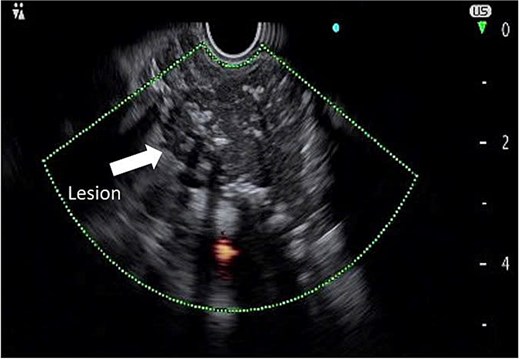

To further characterize the lesion, endoscopic ultrasound (EUS) was performed, which revealed a hypoechoic mass with clear margins, internal calcifications, and abundant vascularity (Fig. 2). A fine needle biopsy (FNB) using a 22G needle yielded multiple lymphoid cells, but the sample was insufficient for a definitive diagnosis. Given the inconclusive biopsy and persistent clinical suspicion of malignancy, surgical excision was planned.

Endoscopic ultrasound image demonstrating a hypoechoic mass with defined margins, internal calcifications, and increased vascular flow.

Endoscopic ultrasound (EUS) is useful in evaluating retroperitoneal and peripancreatic neoplasms. Typically, EUS can help distinguish CD from lymphoma. Lesions that are hypoechoic, homogeneous, with clear boundaries and rich blood flow are more likely to be related to UCD [7]. Additionally, UCD tends to have a softer consistency and more abundant blood supply compared to lymphoma [7]. Fine needle biopsy (FNB) presents an opportunity to obtain pathological tissue for histopathological analysis, potentially allowing for a preoperative pathological diagnosis, as seen in the case by Khashab et al. [8]. However, the yield of FNB remains controversial due to low specificity and increased risk of bleeding [9]. In our case, the EUS-guided biopsy was non-diagnostic, consistent with previous reports [10, 11].